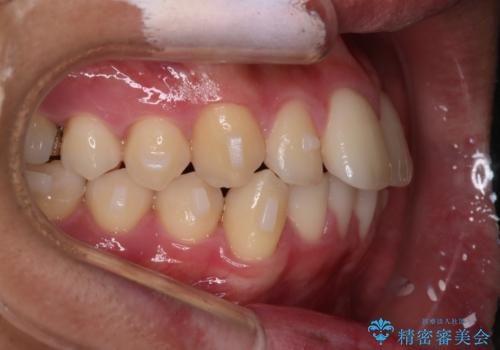

【インビザラインモニター】前歯が出ているのが気になる

- 上の前歯が出ているのが少し気になるとの事で来院されました。

インビザライン希望のため、IPR(歯と歯の間を削る処置)を行うことで、前歯の位置とがたつき整える治療計画を立てました。

患者様よりシュミレーション通りに歯が動くか心配との事だったので

出来るだけ計画通りに歯を動かすために、マウスピース1枚あたりの使用時間を長めに使っていただきました。

そのため、多少治療期間が延びましたが、リファイメント(マウスピースの再発注)なしで終了することができました。